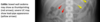

57

Autosomal dominant polycystic kidney disease ## Footnote CT of the abdomen (coronal reformats) demonstrates both kidneys to be markedly enlarged by innumerable cysts ranging in size from a few millimetres to multiple centimetres. These cysts also vary in density: most are near-water density, some are hyperdense, others are calcified. Also present are numerous cysts in the liver. The pancreas is unremarkable. Features are consistent with autosomal dominant polycystic kidney disease, which was subsequently confirmed.

58

Sigmoid volvulus ## Footnote dilation causes the classic coffee-bean sign, a pathognomonic of sigmoid volvulus.